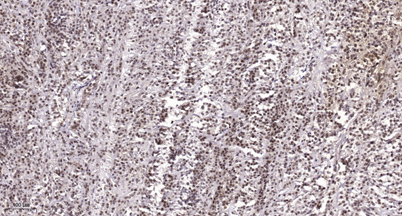

| Dilutions: | Western Blot: 1/500 - 1/2000. Immunohistochemistry: 1/100 - 1/300. Immunofluorescence: 1/200 - 1/1000. ELISA: 1/10000. Not yet tested in other applications. |